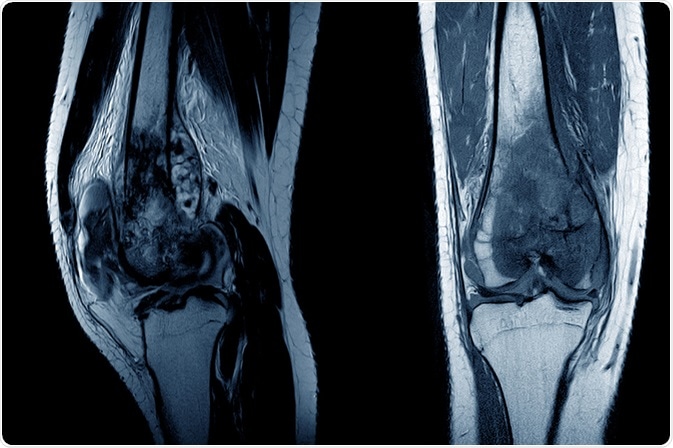

osteosarcomaMRI of a knee joint showing osteosarcoma. Image Credit: April stock / Shutterstock.com